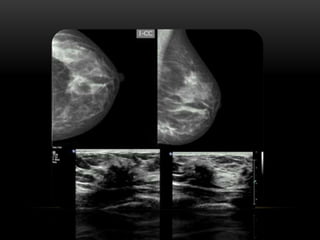

PATRÓN DE TEJIDO

PATRÓN DEL TEJIDO GLANDULAR

FIBROGLANDULAR ESCASA CANTIDAD

FIBROGLANDULAR MODERADA CANTIDAD